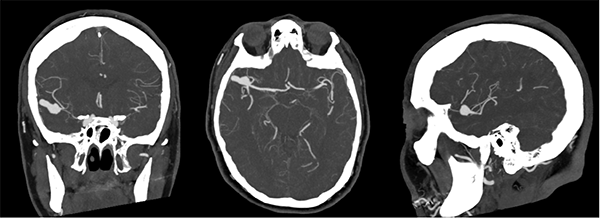

Figura 2:

Se observa en Angiotomografía de vasos intracraneanos en sus tres cortes anatómicos a nivel de la bifurcación de la arteria cerebral media derecha una dilatación aneurismática sacular, irregular y polilobulada sin evidencia de signos de trombosis o aterosclerosis.